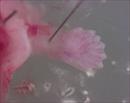

| Immunofluorescence of mutant 012-029-LA collecting duct | Cplane1b2b012Clo/Cplane1b2b012Clo | C57BL/6J-Cplane1b2b012Clo |

| Immunofluorescence of mutant 012-029-LA ureteric bud. Cilia in ureteric buds and collecting ducts are shorter than normal | Cplane1b2b012Clo/Cplane1b2b012Clo | C57BL/6J-Cplane1b2b012Clo |

| Immunofluorescence of mutant 012-033-2 (E15.5) ureteric bud with very short cilia | Cplane1b2b012Clo/Cplane1b2b012Clo | C57BL/6J-Cplane1b2b012Clo |